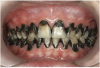

Fig 8. Use of 38% SDF to arrest rampant caries in a young teenager: pre-treatment intraoral frontal view of rampant caries. (image from Chu, et al, 2014, ref 36 [reprinted with approval])

Figure 8

Fig 9. Use of 38% SDF to arrest rampant caries in a young teenager: frontal view of arrested caries after consecutive application of SDF for 3

weeks. (image from Chu, et al, 2014, ref 36 [reprinted with approval])

There is no consensus on the frequency of application, and 38% SDF has been used annually or biannually on clinical trials in children23,31,33,34 and in elderly.30,35 Yee and his co-worker found one-off application of 12% SDF was ineffective in arresting caries in children.31 The present authors applied 38% SDF weekly for 3 weeks to speed up the process of caries arrest and for treatment of rampant caries.36 One of the present authors’ case reports demonstrated that three weekly applications of 38% SDF can arrest rampant caries and relieve pain from hypersensitivity on a teenager. The SDF-treated caries were found arrested, and they turned coal black in appearance (Figure 9).